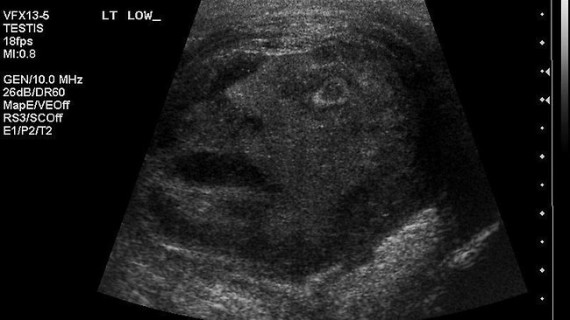

The screaming face that you see above you came from ultrasound images of the scrotum of a 45-year-old man , and was recently published in the journal Urology in an article entitled, “The Face of Testicular Pain: A Surprising Ultrasound Finding.”

While scrolling through the ultrasound images, the residents and staff alike were amazed to see the outline of a man’s face staring up out of the image, his mouth agape as if the face seen on the ultrasound scan itself was also experiencing severe pain.

A brief debate ensued on whether the image could have been a sign from a deity (perhaps Min the Egyptian god of male virility); however, the consensus deemed it a mere coincidental occurrence rather than a divine proclamation.

The testicle was removed and the screaming face tumor turned out to be benign.